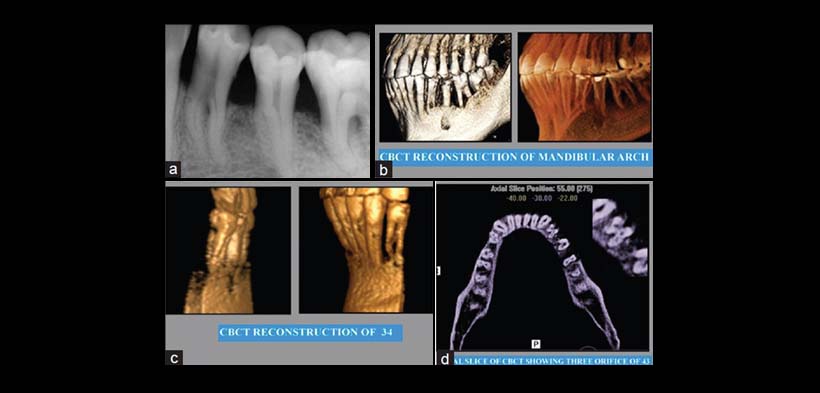

Figura 1. (a) Radiografía periapical preoperatoria mostrando al primer y segundo premolar y al primer molar inferior. (b) Reconstrucción 3D de la tomografía de haz cónico. (c) Cone beam reconstrucción tomografía computarizada de la pieza 3.4. (d) Corte axial de la tomografía computarizada de haz cónico que muestra la presencia de 3 conductos radiculares de las primeras premolares inferiores.